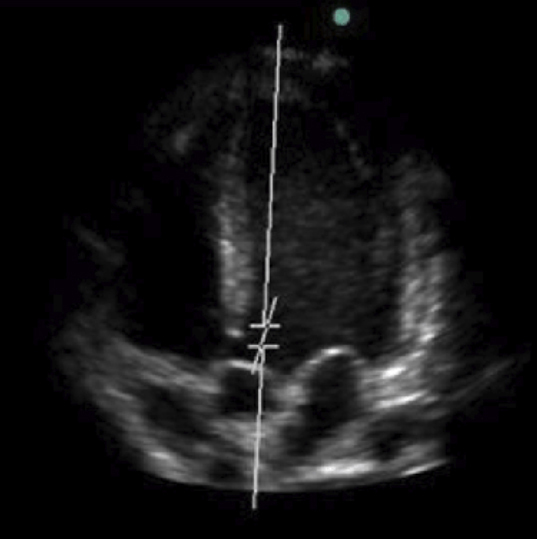

Vous réalisez une ETT. Celle-ci retrouve une valve aortique calcifiée avec les valeurs suivantes : Vmax à 3,8 m/s, gradient moyen à 32 mmHg et surface aortique à 0,55 cm²/m². On note également un index cardiaque abaissé, à 1,5 L/min/m² .

Figure 1 (Elon Zerah, La Revue du Praticien)

Question 3 - À propos de cet examen, vous affirmez (une ou plusieurs réponses exactes) :

Une ETT se réalise en plaçant le patient en décubitus latéral gauche pour rapprocher le cœur de la paroi thoracique et augmenter l’échogénicité.

On distingue les 2 oreillettes, les 2 ventricules ainsi que l’aorte, il s’agit donc bien d’une coupe apicale 5 cavités.

On visualise la valve tricuspide entre l’oreillette droite et le ventriculaire droit, la valve mitrale entre l’oreillette gauche et le ventricule gauche, ainsi que la valve aortique dans la chambre de chasse ventriculaire gauche. La valve pulmonaire ne peut pas être visualisée sur cette coupe :

Pour que le RA soit serré, il faut obtenir un de ces trois critères :

– Vmax > 4 m/s

– gradient moyen > 40 mmHg

– surface aortique < 1 cm² ou 0,6 cm²/m².

L’administration de dobutamine augmente le débit cardiaque, donc la quantité de sang qui passe par la valve aortique rétrécie. Logiquement, cela s’accompagne d’une augmentation du gradient de pression aorte-ventricule gauche. Dans le cas présent de RA associé à un bas débit, l’administration de dobutamine permettrait d’augmenter le gradient moyen au-dessus de 40 mmHg.

Il faut maîtriser les principales coupes à l’ETT pour identifier les différentes structures anatomiques intra-cardiaques : apicales 2, 3, 4 et 5 cavités, para-sternale grand axe et sous-costale.

L’ETT retrouve un RA serré.